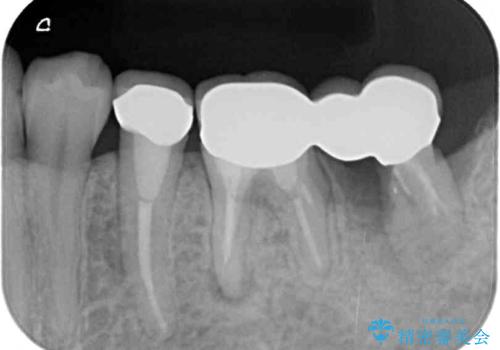

- 抜歯が必要と診断された奥歯の治療を希望して来院された患者様です。

一番奥の歯は歯根の一部を残した状態で、手前の歯とブリッジが装着されていました。

奥歯は歯根周辺の歯槽骨が広範囲に失われており、抜歯が必要と判断されました。

ブリッジの手前側の歯は、根管治療が必要な状態でした。